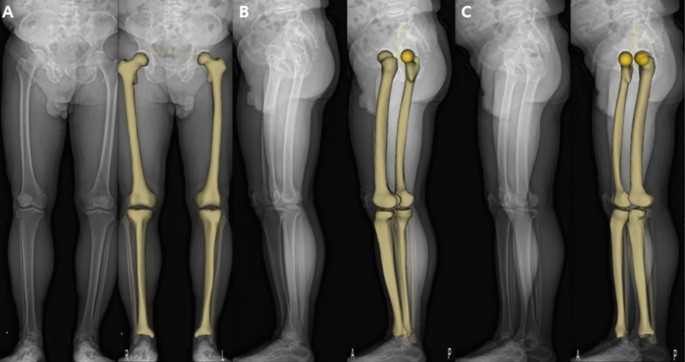

Whatsapp x WhatsApp Number Message phone x email x info@imagesradiologycom If you know, EOS is a low dose weight bearing XRay technology Images of the human body or the skeletal system can be produced in 2D or 3D form Contact us Home;The EOS Imaging System is a revolutionary advance in xray imaging Using Nobel Prizewinning technology, the ultralowdose system scans our patients in an upright, weightbearing position in seconds This allows the doctor to see the natural way that their joints interact with their musculoskeletal system, making it ideal for diagnosing

Eos x ray system-EOSedge EOSedge is a precise, low dose imaging system that delivers full body, highquality images covering the full set of musculoskeletal and orthopedic exams This next generation solution captures fully functional 2D/3D biplanar images in seconds, using a highresolution photoncounting detector for outstanding image quality for a broad range of patientsEOS imaging is a medical device company based in Paris, France, that designs, develops, and markets EOSedge and the EOS system, innovative, orthopedic medical imaging systems, associated with several orthopedic solutions along the patient care pathway – from diagnosis to postoperative treatments The EOS platform targets musculoskeletal disorders and orthopedic

The new EOS Xray system uses significantly lower radiation in the diagnosis of scoliosis Patients stand or sit inside the imaging system while it takes spAbstract Background EOS is a biplane Xray imaging system manufactured by EOS Imaging (formerly Biospace Med, Paris, France) It uses slotscanning technology to produce a highquality image with less irradiation than standard imaging techniques Objective To determine the clinical effectiveness and costeffectiveness of EOS twodimensional (2D)/threedimensional (3D) X The EOS™ Xray machine, based on a Nobel prizewinning invention in physics in the field of particle detection, is capable of a simultaneous capture of biplanar Xray images by slot scanning of the whole body in an upright, physiological loadbearing position, using ultralow radiation doses

EOS is highly efficient as this imaging system uses low does of radiation compared to the other MRIs It can give the physicians a better hand to preplan the treatment for the children which can bring out effective results An EOS scan can effectively show the child’s natural weight bearing posture and even allows us to see the interaction between joints and hips, spine and legs EOS Xrays produce highquality detailed images and expose patients to significantly lower doses of radiation than traditional Xrays “An EOS imaging system is important for kids with scoliosis because the radiation dose is about 1/7th of a normal Xray dose at the initial visit and much lower still for followup Xrays using the microdoseNo evidence was found on the impact of EOS on patients' pathways of care or ultimate health outcomes Radiation dose is considerably lower with EOS than CR or film Xray imaging, whereas image quality remains comparable or better with EOS Patient throughput is the major determinant of the costeffectiveness of EOS